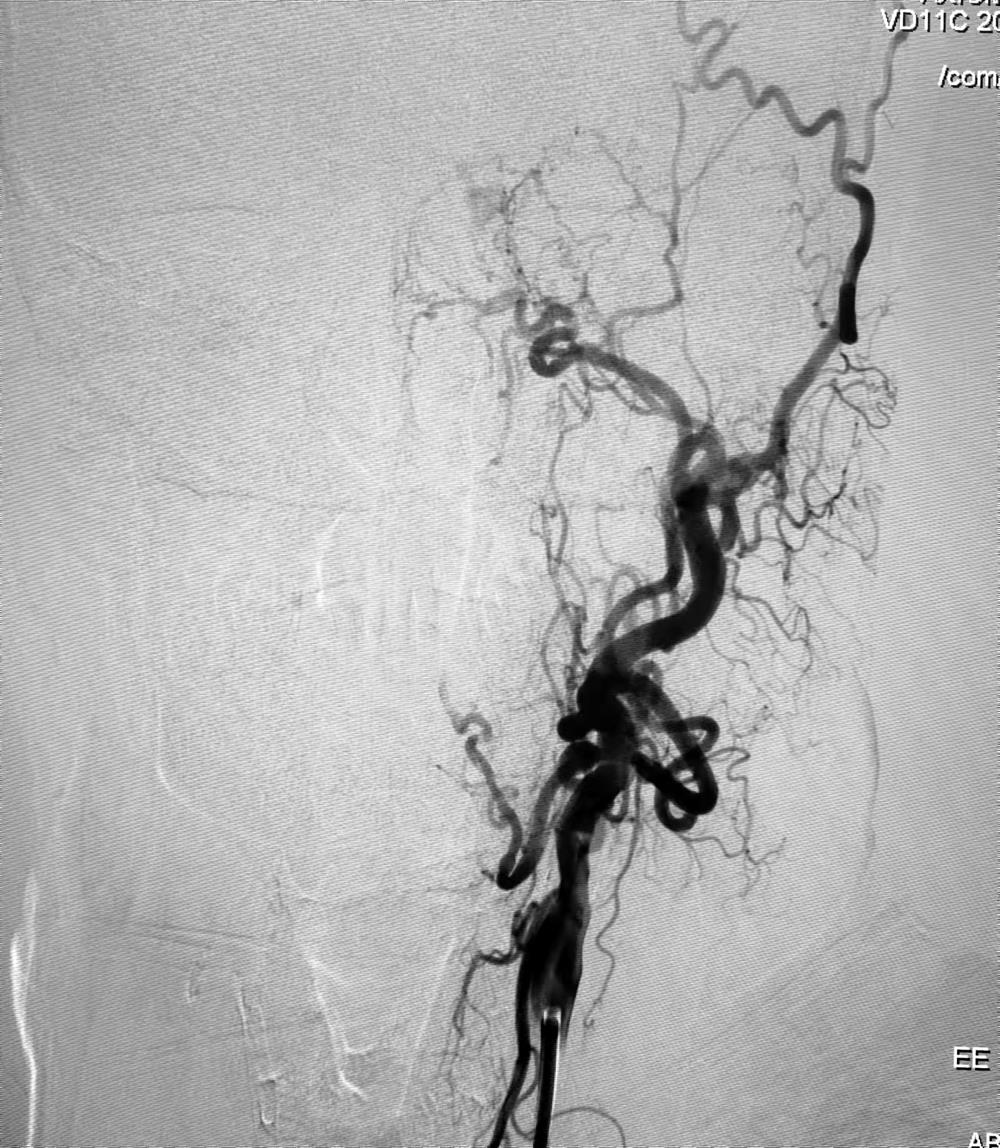

术前DSA

70岁的患者朱某,1个月前主因“突发言语不清9个小时”由外院转入榆林二院脑科医院神经外科一病区。入院时,MRI提示左侧额顶叶脑梗死,急诊全脑血管造影提示左侧颈内动脉慢性闭塞。入院后患者症状逐渐好转,考虑到患者年龄和介入开通风险,家属未行积极的介入开通治疗,暂考虑行保守治疗。